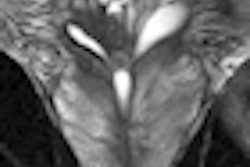

With the UroNav technology, a patient is scanned with MRI before undergoing a biopsy, and during the biopsy the MR and ultrasound images are fused. UroNav then employs GPS-type technology to guide the biopsy needle to the lesions detected by MRI, leading to fewer needle biopsies.

Loyola prostate cancer surgeon Dr. Gopal Gupta said the new technology could help prevent physicians from missing hard-to-find and often-aggressive prostate cancers, providing greater certainty regarding the extent and aggressiveness of the disease.